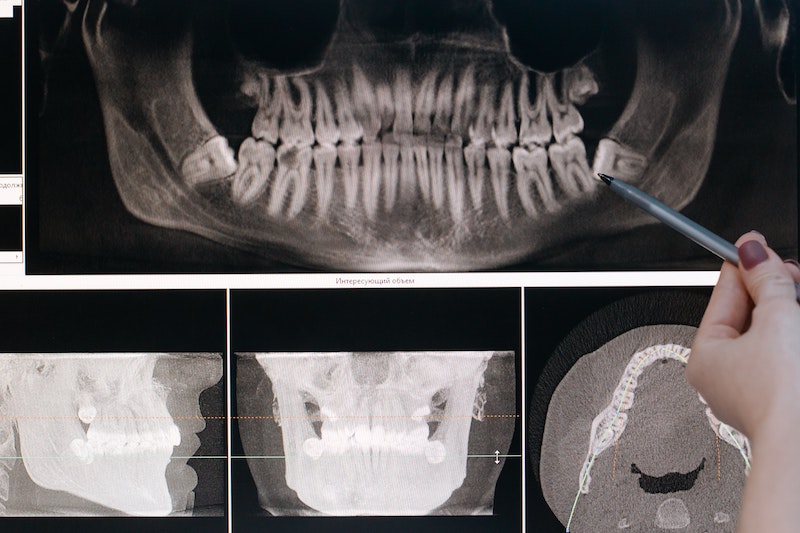

Typically the highest-paid type of dentist is an Oral and Maxillofacial Surgeon (OMFS). This is the dentist whose job is the most invasive of all dentists. Typically Oral surgeons use sedation options to remove wisdom teeth, place dental implants, perform bone grafts, and much more. They go through rigorous training and education well past many of their colleagues due to these advanced medical procedures. Therefore, the typical salary for an Oral Surgeon can range anywhere from $250,000 to $400,000 per year (or more). Usually, the average salary for an Oral Surgeon is around $310,000 per year.